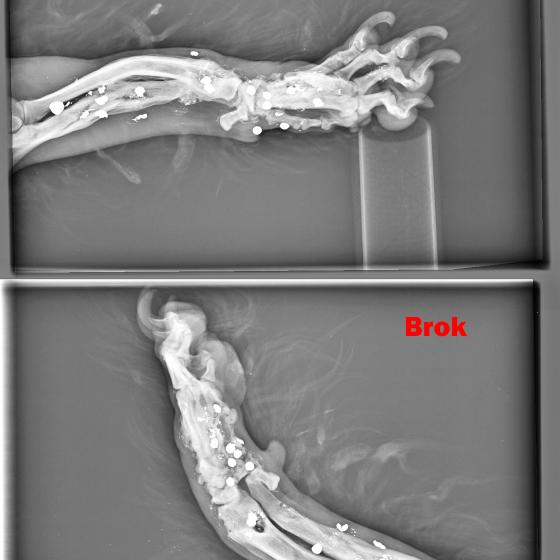

BROK - dostal meno Brok, keďže sa stal živým terčom a má vo svojom malom telíčku nespočetné množstvo brokov. Labka je vykrivená preto, že sa mu v dôsledku streľby dolámali kosti...

Image removed.BROK - dostal meno Brok, keďže sa stal živým terčom a má vo svojom malom telíčku nespočetné množstvo brokov. Jeho brata sme odchytili pár mesiacov pred ním, keď do neho deti hádzali petardy. On z toho vyviazol bez problémov, ale žiaľ Brok to šťastie už nemal. Jeho celá nožička je zdeformovaná, dostieľaná, dolámaná. On nenatrafil na deti, ale na dospelého, zjavne psychicky narušeného človeka, ktorý mu neskutočne ublížil. Odpusťte mi, keď do prosby vnesiem aj emócie, ale pri pohľade na neho sa topím v slzách. Brok je jeden z najláskavejších psíkov akého sme kedy mali. Miluje ľudí, objíma ich aj tou boľavou nožičkou. Rozdáva pusinky každému. Má celý život pred sebou. Tak rád by bezstarostne behal a naháňal sa, ale potkne sa aj o vlastnú nohu. Skáče na človeka, akoby sa odprosoval, že už nikdy viac nebude neposlušný, len nech mu už nikto neublíži. Chce dokázať, že je dobrý, že nadovšetko miluje a nechce ho pustiť, už nikdy viac nechce byť bez svojho človeka. Toľko toho ešte môže a musí zažiť! Potrebuje svoju nožičku a musíme mu pomôcť. Bude to nákladné, ale toto je jednoducho situácia, ktorú musíme vyriešiť a dopriať mu plnohodnotný život. Brok má v nešťastí obrovské šťastie. Keď sme si mysleli, že jediným riešením bude amputácia, ujal sa ho najlepší ortopéd v republike, MVDr. Vatolík a nožičku mu vie napraviť. Bročko ale potrebuje Vašu pomoc, lebo bez nej to nepôjde. Diagnostiku a prvú operáciu, odstránenie brokov z tkaniva má už úspešne za sebou. Zatiaľ má "len" malé ranky, z ktorých sa rýchlo zotaví. Momentálne čakáme na výsledky kultivácie. Tkanivo musí byť "čisté" bez akejkoľvek infekcie, bez akýchkoľvek baktérií, aby sa mohlo ďalej pokračovať.

Labka je vykrivená preto, že sa mu v dôsledku streľby dolámali kosti a keď sme ho našli, už bolo všetko zahojené a zle zrastené. Za diagnostiku a prvý zákrok máme faktúru vo výške 449,23€.

Ďalšia operácia, ktorá ho čaká 21.5.2020 bude ale veľmi náročná. Treba odstrániť broky z kostí, a tým pádom bude treba vyrezať časť zlomených a zle zahojených kostí v nožičke. Tieto časti sa následne nahradia implantátmi (pán doktor ešte zvažuje či použiť implantáty z titánu, ktoré sú prijateľnejšie pre organizmus, alebo implantáty z chirurgickej ocele, ktorá je pevnejšia). Bročko bude mať v nožičke vnútorné fixátory, ktoré ju budú držať pokope, kým sa opäť nezocelí. Nebude to žiadna prechádzka ružovou záhradou, ale zvládneme to! Z našej strany pre neho urobíme všetko a doprajeme mu plnohodnotný a bezstarostný štart do nového života. Potrebujeme ale Vašu pomoc. Náklady na operáciu sa predpokladajú do výšky okolo 1500€. Celkom teda za Bročka cca 2000€.